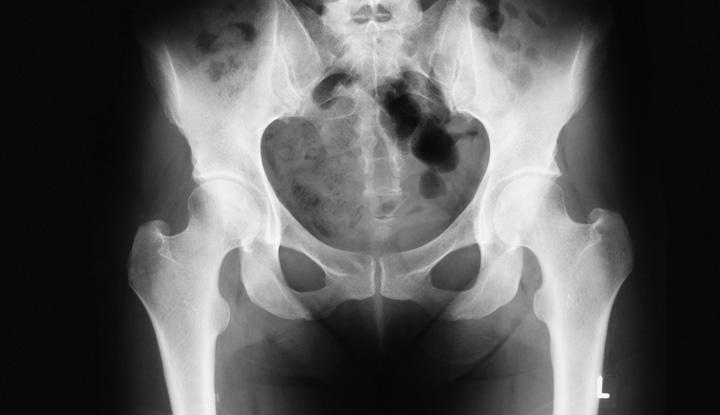

A pelvis X-ray (radiograph) is a medical imaging test that creates a black-and-white picture of your pelvic bones. Your pelvic bones include your hip bones (ilium, ischium and pubis), the triangle-shaped bone at the base of your spine (sacrum) and your tailbone (coccyx). Healthcare providers use pelvis X-rays to diagnose and treat medical conditions that affect the area in and around your pelvis.

Your body parts vary in thickness, so they take in different amounts of radiation. Calcium in your bones takes in more radiation, so your bones appear white on the X-ray. Soft tissues take in less radiation, so they appear in different shades of gray. Air appears black. If you have a broken bone, the bone will appear white and a black line running through the bone will show the fracture.

Does a normal pelvis X-ray look like it’s cracked?

The bones of your pelvis and hips fit together like a puzzle. Once the puzzle is complete, you can still see the outline of each piece. Children’s hip bones and pelvis bones aren’t completely fused together yet, so the spaces between the bones look wider.

Male pelvis X-rays and female pelvis X-rays can show the differences in bone structures between malesand females. An adult male pelvis is narrower than a female pelvis. An adult female pelvis is usually broader than a male pelvis. The male pelvis is more oval or heart-shaped. The female pelvis is rounder. Also, the angle of the pubic arch in a male pelvis is less than 90 degrees. The angle of the pubic arch in a female pelvis is more than 90 degrees.